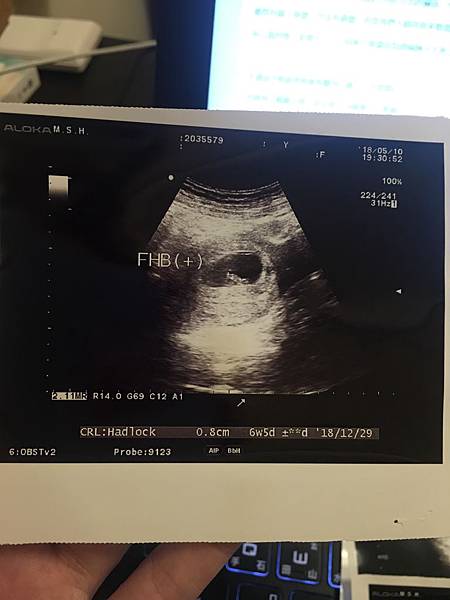

因為有聽說最好要等到小紅過期一個多禮拜再去看醫生照超音波會比較看得見,

所以雖然很早就驗出兩條線了,但我們還是等了一小段時間才去照超音波。